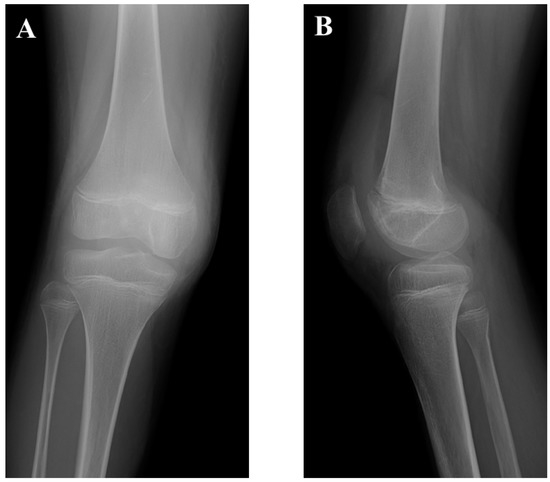

2. Case Presentation